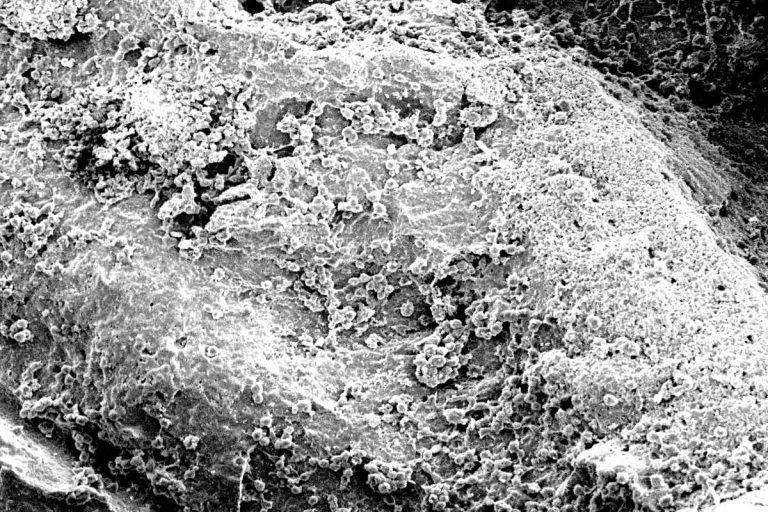

cerabone ® es un mineral de hueso 100% puro de origen bovino fabricado por un proceso único de producción 1200 ° C. Se ha aplicado con éxito en más de 1 millón de pacientes en odontología regenerativa y se ha utilizado durante más de 15 años en diversas aplicaciones médicas (por ejemplo, cirugía craneofacial, oncología y cirugía de manos y columna).

El sofisticado procesamiento del hueso bovino elimina todos los componentes orgánicos dando como resultado un mineral óseo con una pureza excepcional . Además, los posibles agentes infecciosos, como bacterias, virus y priones, se eliminan mediante el tratamiento a alta temperatura. Tanto el producto como el proceso de producción cumplen con los requisitos normativos y de seguridad nacionales e internacionales aplicables para los injertos óseos bovinos, incluidas las normas ISO 22422-1, ISO 22442-2 e ISO 22442-3.

– Superficie rugosa e hidrofílica